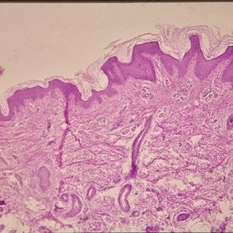

Histopathology of Linear Sebaceous Nevus Syndrome

Histopathology of Linear Sebaceous Nevus Syndrome

Feb 20 2015 by H. Michael Lambert, MD

Histopathology of linear sebaceous nevus syndrome.

Condition/keywords: histopathology, linear nevus sebaceous syndrome